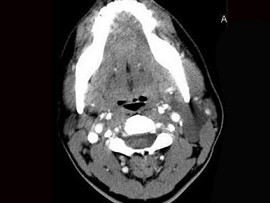

| 八岁患者,男性,因颈前正中包块6年入院,查体:颈前正中舌骨下方可触及一圆形包块,囊性,无压痛,随吞咽上下活动。 |

8.患者肿块图像及影像学检查结果见下图,本患者应考虑为 ( )![]() ![]() ![]() ![]() |

| 正确答案:8.A;9.A |